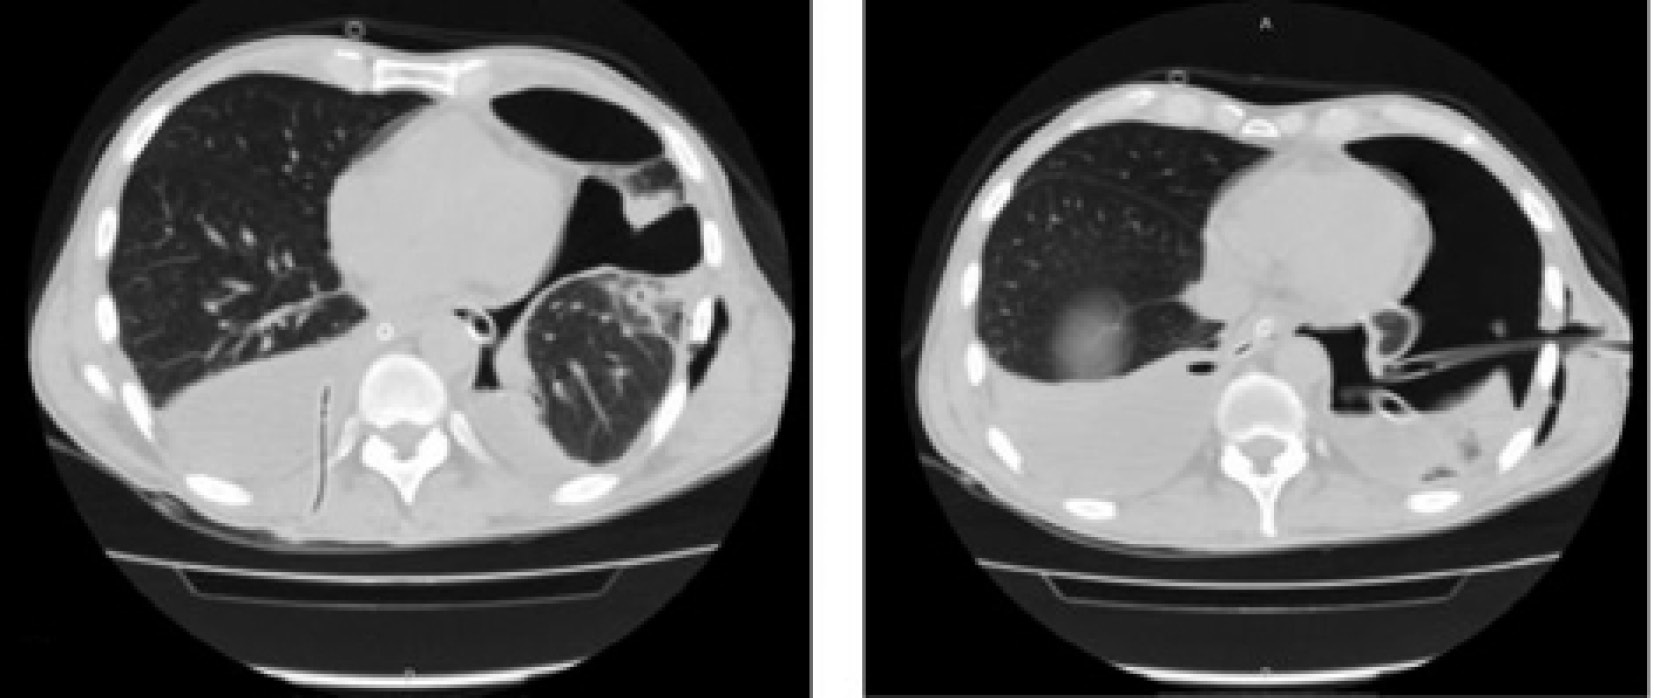

При спиральной компьютерной томографии груди диагностирован затек контраста в обе плевральные полости, признаки медиастинита (рис. 2).

Рис. 2. Компьютерные томограммы (А и Б) в аксиальной проекции. Двусторонний гидроторакс, слева гидропневмоторакс на фоне энтерального зонда и дренированных плевральных полостей